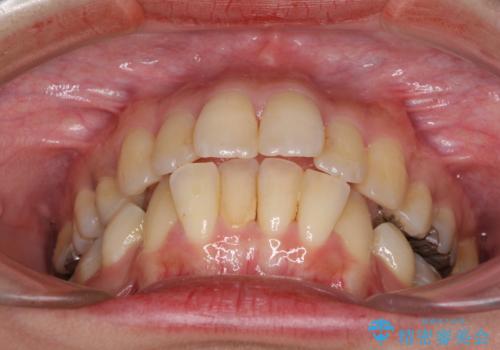

舌の突出癖がなかなか改善できず、IPRによる前歯の隙間が閉じきらずに、予定よりも長い治療期間となりました。

- 抜歯矯正の後戻りで前歯が突出してきていることを気にして来院された患者様です。

口元の突出感を改善するにあたり、抜歯矯正は行うことができないため、奥歯の後方移動とIPR(歯と歯の間を削る)により達成することとしました。

再度後戻りしたときに対応しやすいよう、インビザラインにて矯正治療を行うこととしました。